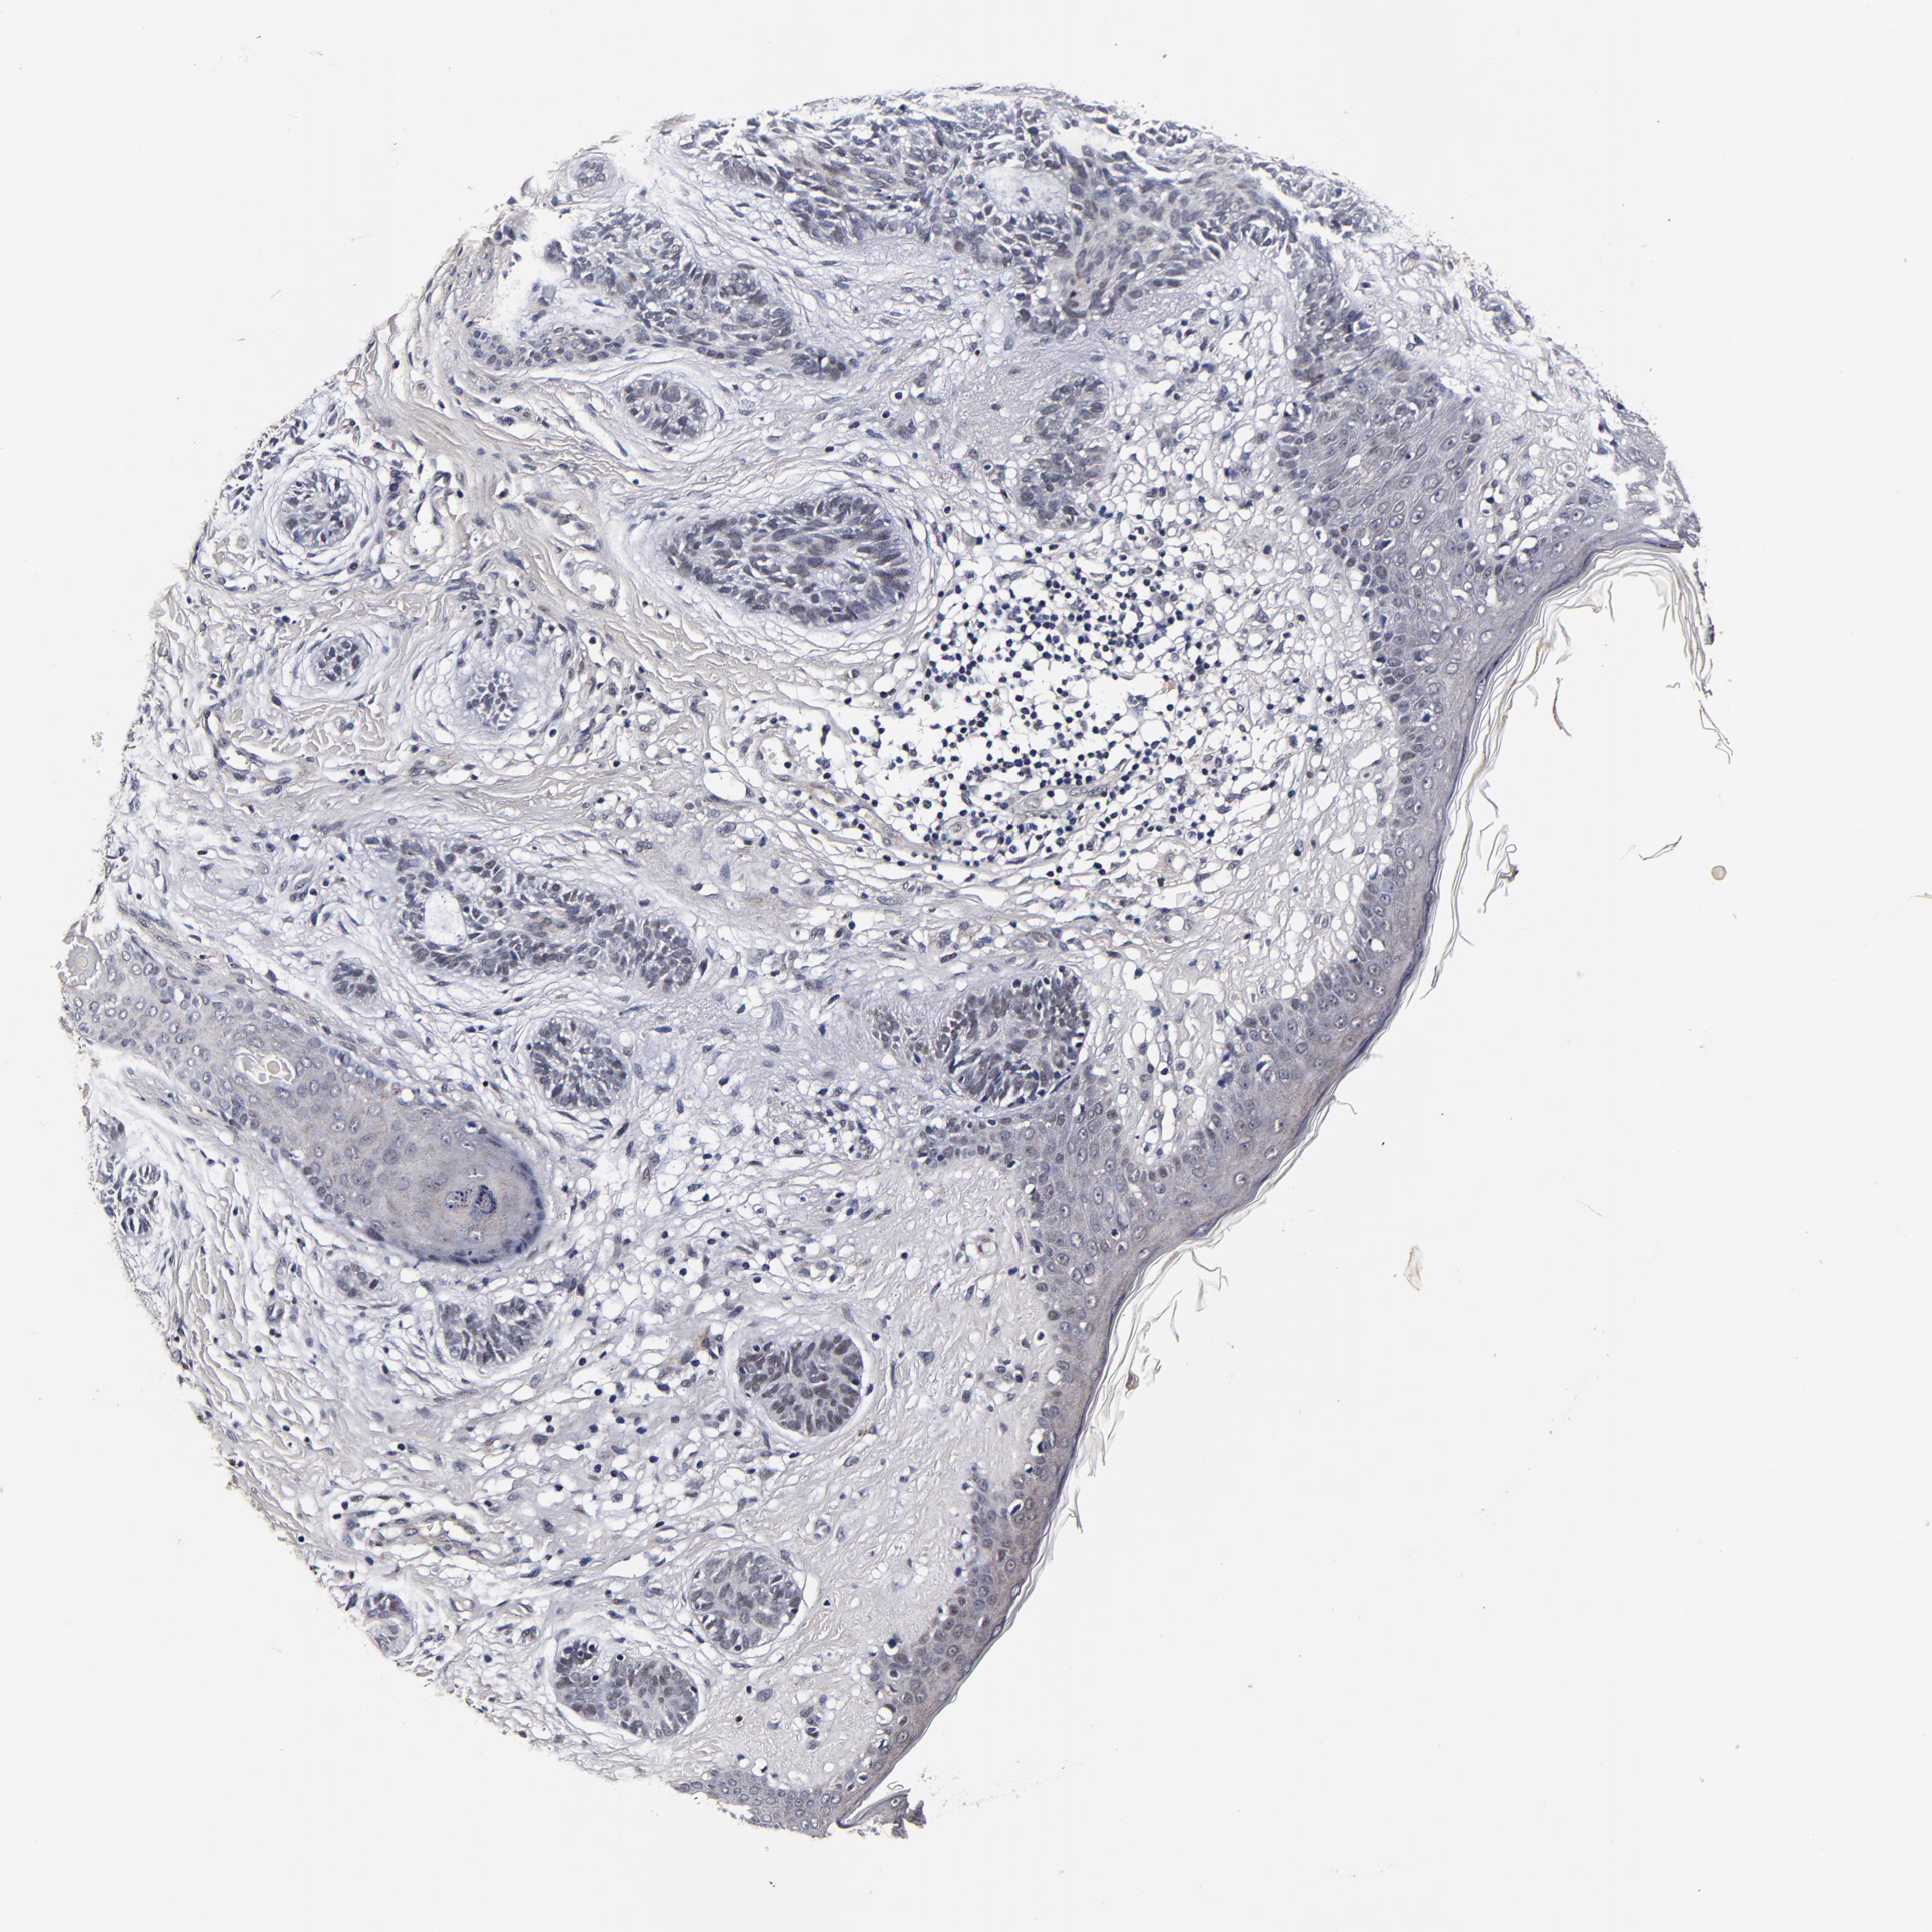

Basal cell and squamous cell cancer

SKIN CANCER - Protein expressioni

A mouse-over function shows sample information and annotation data. Click on an image to view it in a full screen mode. Samples can be filtered based on level of antibody staining by selecting one or several of the following categories: high, medium, low and not detected. The assay and annotation is described here.

Antibody stainingi

Antibody staining in the annotated cell types in the current human tissue is reported as not detected, low, medium, or high, based on conventional immunohistochemistry profiling in selected tissues. This score is based on the combination of the staining intensity and fraction of stained cells.

Each image is clickable and will lead to virtual microscopy that enables deeper exploration of all samples and also displays staining intensity scores, fraction scores and subcellular localization as well as patient and tissue information for each sample.

Antibody HPA040390

Basal cell carcinoma